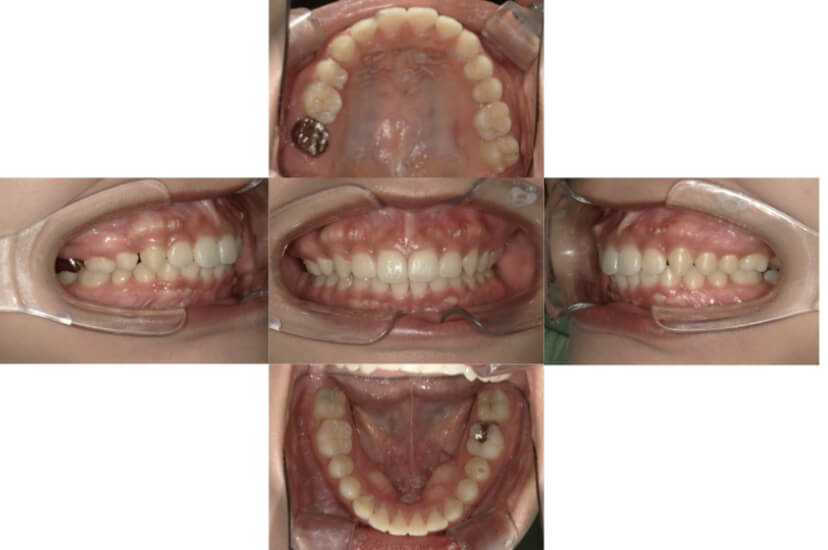

BEFORE

AFTER

上下顎前突、叢生(上下出っ歯、上下の前歯のガタガタ)のケースです。

装置はラビアル(上下表側)で、上下顎の小臼歯を4本抜歯を行っています。抜歯したスペースを使って、上下の前歯の後方移動と叢生(ガタガタ)の改善を行っています。

主訴 前歯のガタガタと口元がでているのが気になる。

年齢・性別 30歳 女性

お住まいの地域 東京都大田区

治療方針 抜歯スペースを利用して上前歯の叢生(ガタガタ)と口元突出の改善

抜歯部位 上下顎左右第一小臼歯

使用装置 ラビアル(上下表側)、顎間ゴム

治療期間 1年11か月

治療回数 13回

リテーナー クリアリテーナー